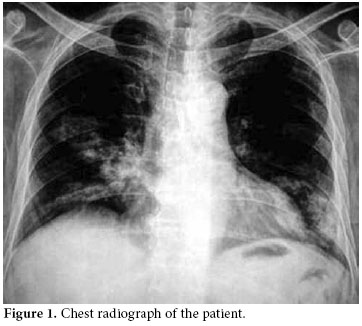

A 50-year-old male patient was admitted to our hospital with symptoms of fatigue, proximal muscle weakness, and bruising. Two years previously, he had manifested symptoms of arthralgia, arthritis, and edema. Because of these complaints, laboratory tests were performed. Nephrotic range proteinuria, a high creatinine level, bicytopenia along with antinuclear antibody (ANA) and Anti-deoxyribonucleic acid (anti-DNA) positivity were determined in these tests. Systemic lupus erythematosus was considered. Type ΙV lupus nephritis was also determined with a kidney biopsy. Endoxan 500 mg pulse and methylprednisolone 1000 mg pulse (3 days) were given to the patient parenterally. After these immunosuppressive treatments, the symptoms of the patient relieved, and corticosteroid treatment was continued as methylprednisolone 1 mg/kg/day at another hospital. The methylprednisolone dosage was not tapered accordingly, and after four months, suffering from fatigue, proximal myopathy, and weakness and the patient was admitted to our clinic. Upon physical examination, no other finding other than proximal muscle weakness was determined. Laboratory findings were white blood cell count: 12300/mm3, hemoglobin: 8.9 g/dl, hematocrit: 24%, MCV: 82 fL, lymphocyte: 200 mm3, platelet: 63000 mm3. Glucose: 79 g/dl, BUN: 109 mg/dl, creatinine: 2.7 mg/dl, uric acid: 8.4 mg/dl, Na: 135 mmol/L, K: 4.6 mmol/L, Cl: 105 mmol/L, Calcium: 8.2 mg/dl, P: 4.0 mg/dl, AST: 12U/L, ALT:39 U/L, LDH: 643 U/L, ALP: 70 U/L, and anti-dsDNA of 1:1280. Total bilirubin: 0.48 mg/dl, direct bilirubin: 0.06 mg/dl, Indirect bilirubin: 0.42 mg/dl, total protein: 5 g/dl, albumin: 2.39 g/dl, Fe: 73 mcg/dl, Iron binding capacity: 212 mcg/dl., PT: 11.1 sn, aPTT: 18.8 sn, INR: 0.90 were found. A chest radiograph taken on admission revealed multiple cavitary lesions (Figure 1). A chest computed tomography (CT) also showed multiple cavitary lesions at the sites of the right medial lobe, right inferior lobe superior segment, and left lingula inferior segment along with nodular lesions at the right inferior lobe superior segment (Figure 2). These lesions were found to be related with intensive and long-term steroid treatment. The cavitary lesions were considered as an opportunistic fungal infection, nocardiosis, or tuberculosis. A smear of sputum was negative for both Gram stain and acid fast bacilli, and cultures related to tuberculosis were found to be negative. A bronchoscopy and endobronchial lavage were performed to determine the etiology of these lesions. No endobronchial lesion was observed. Cultures for tuberculosis, nocardiosis, and fungal infections were taken from bronchoalveolar lavage, and also samples were taken for cytologic examination of lavage. In bronchoalveolar lavage fluid cytology, polymorphonuclear leukocytes was detected, and there were no atypical findings. The sputum specimen was also examined again, and cultures were sterile. The symptoms of the patient had increased progressively. The cavitary lesions had also increased. Because of this progression, high resolution computed tomography (HRCT) was performed. New cavitary lesions were determined at the left pulmonary site in HRCT. Nocardiosis was found positive in bronchoalveolar lavage fluid specimens. The patient was diagnosed as having pulmonary nocardiosis and given intravenous trimethoprim-sulfamethoxazole (320 mg/1600 mg/day), but the patient’s clinical findings worsened. Acute respiratory failure developed on the second day of treatment. Metabolic acidosis and respiratory alkalosis were added to the clinical findings. In arterial blood gas, PH: 7.31, PCO2: 24.8 mmHg, PO2: 35.6 mmHg, HCO3: 12.2 mmol, O2 saturation: 57.9% were found. Oxygen inhalation and anti-obstructive treatment were started. Sepsis and acute respiratory distress syndrome were considered possible , and the patient was sent to the intensive care unit. The patient died one day after being sent to the intensive care unit.

Pulmonary nocardiosis produces an impressive variety of roentgenographic findings, such as segmental infiltrates, lobar infiltrates, small and large cavities, necrotizing bronchopneumonia, necrotizing lobar pneumonia, lobar pneumonia with bulging fissures, small and large abscesses, single or multiple nodules, miliary patterns, masses with central cavitations, pleural effusion, and empyema.[5] Because the radiographic feature of nocardiosis is non-specific and pleomorphic with clinical findings ranging from malaise to respiratory failure, it is difficult to diagnose; therefore, the diagnosis of nocardiosis is often delayed. Multiple nodules and cavitation are more commonly described in acquired immune deficiency syndrome (AIDS) patients.[6,7] Multiple cavitary lesions are very rare in non-HIV patients. In our case, the patient was a man with a diagnosis of SLE, and he had undergone corticosteroid treatment for a long time. Although his test was negative for AIDS, multiple cavitary lesions were seen in his chest X-ray and HRCT. Since the patient was HIV-negative and immunosuppressive, all causes of multiple cavitary lung lesions were investigated. Tuberculosis, fungal infections, and malignancy were considered in the differential diagnosis. Multiple cavitary pulmonary nodules can be easily confused with a variety of other bacterial infections of the lung, including actinomycosis and tuberculosis as well as fungal infections and malignancies. In our patient, all of these causes were eliminated after all of the necessary tests were performed.

As shown in our case, pulmonary nocardiosis can be found in unexpected ways, especially in immunosuppressed patients. This patient showed multiple cavitary lesions on chest X-rays. The association of nocardiosis with SLE has only been rarely determined, and its association with acute respiratory distress syndrome has only been reported in one case.[14] In our case, acute respiratory failure was also found because of nocardiosis, and although treatment for infection was started, the patient died within a few days.